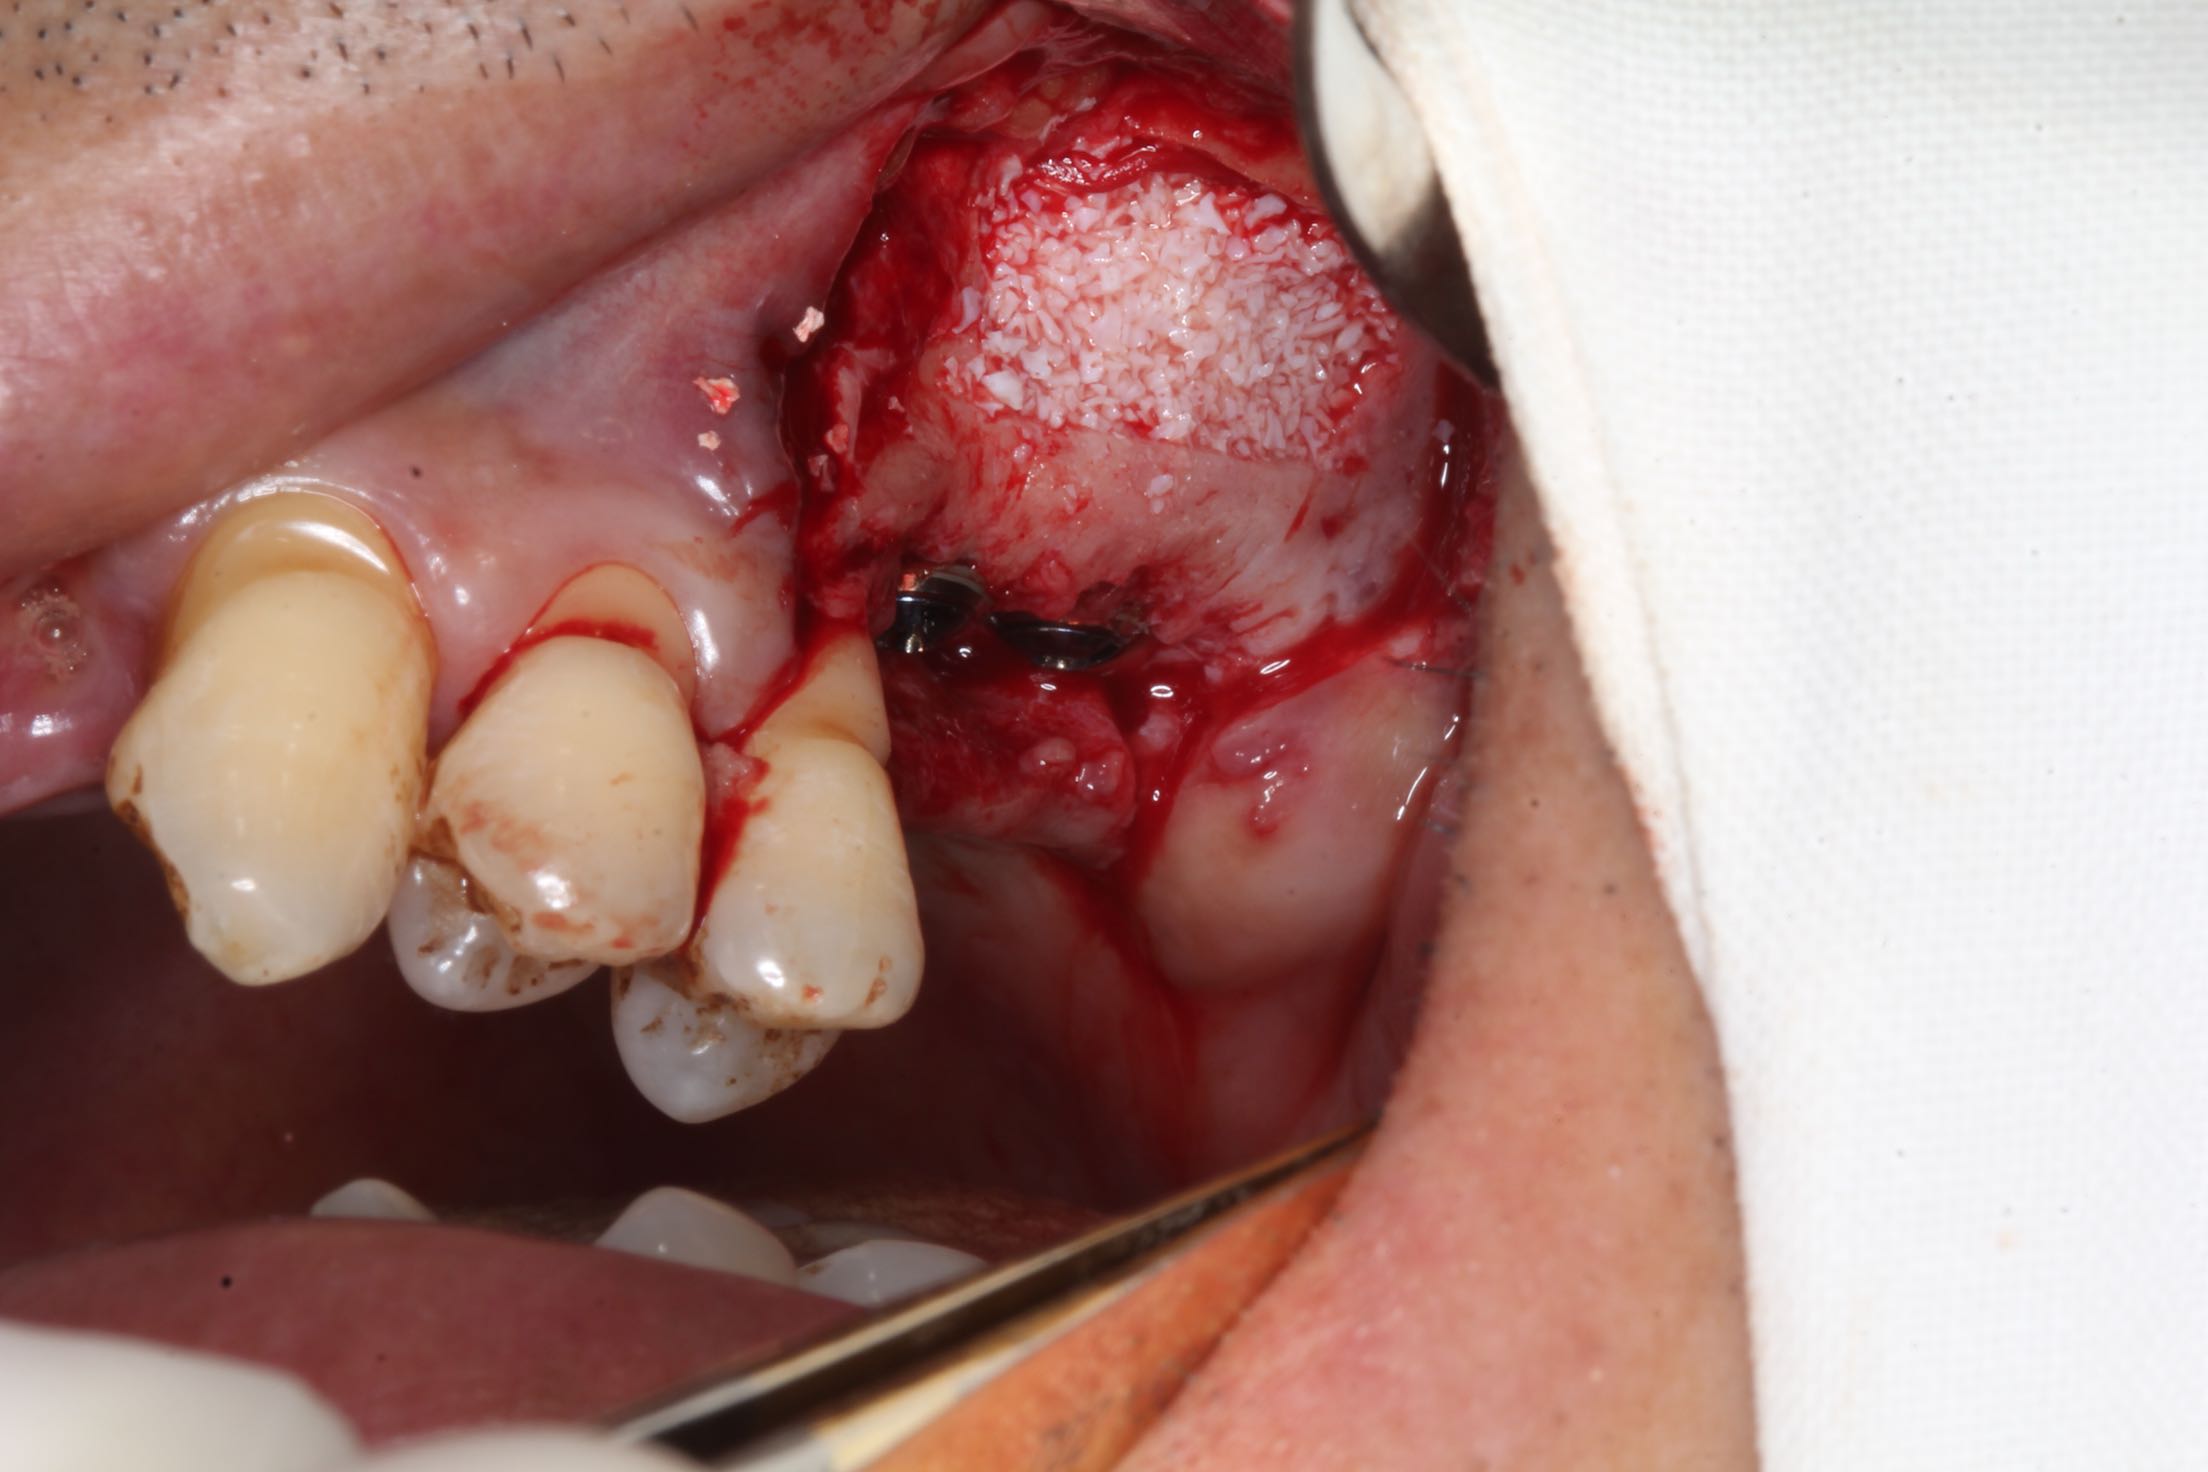

26、27缺失,牙槽骨严重吸收。 治疗:上颌窦外侧壁超刀开窗,取出外侧壁骨块,剥离黏膜,考虑严重吸烟史,黏膜菲薄,垫上一层胶原膜,植入部分Bio-ss骨粉,牙槽嵴顶备洞,26牙植入dentium4.3-10,27牙植入4.3-8,继续植入骨粉共0.5g,开窗处复原骨块,严密缝合!26牙植入扭力35牛,27植入扭力15牛!嘱尽量戒烟,

期待半年后的效果,最主要的挑战:每天15支吸烟史,上颌窦黏膜菲薄,27牙上颌窦底只有2.4mm,超出即刻种植5mm的界限!